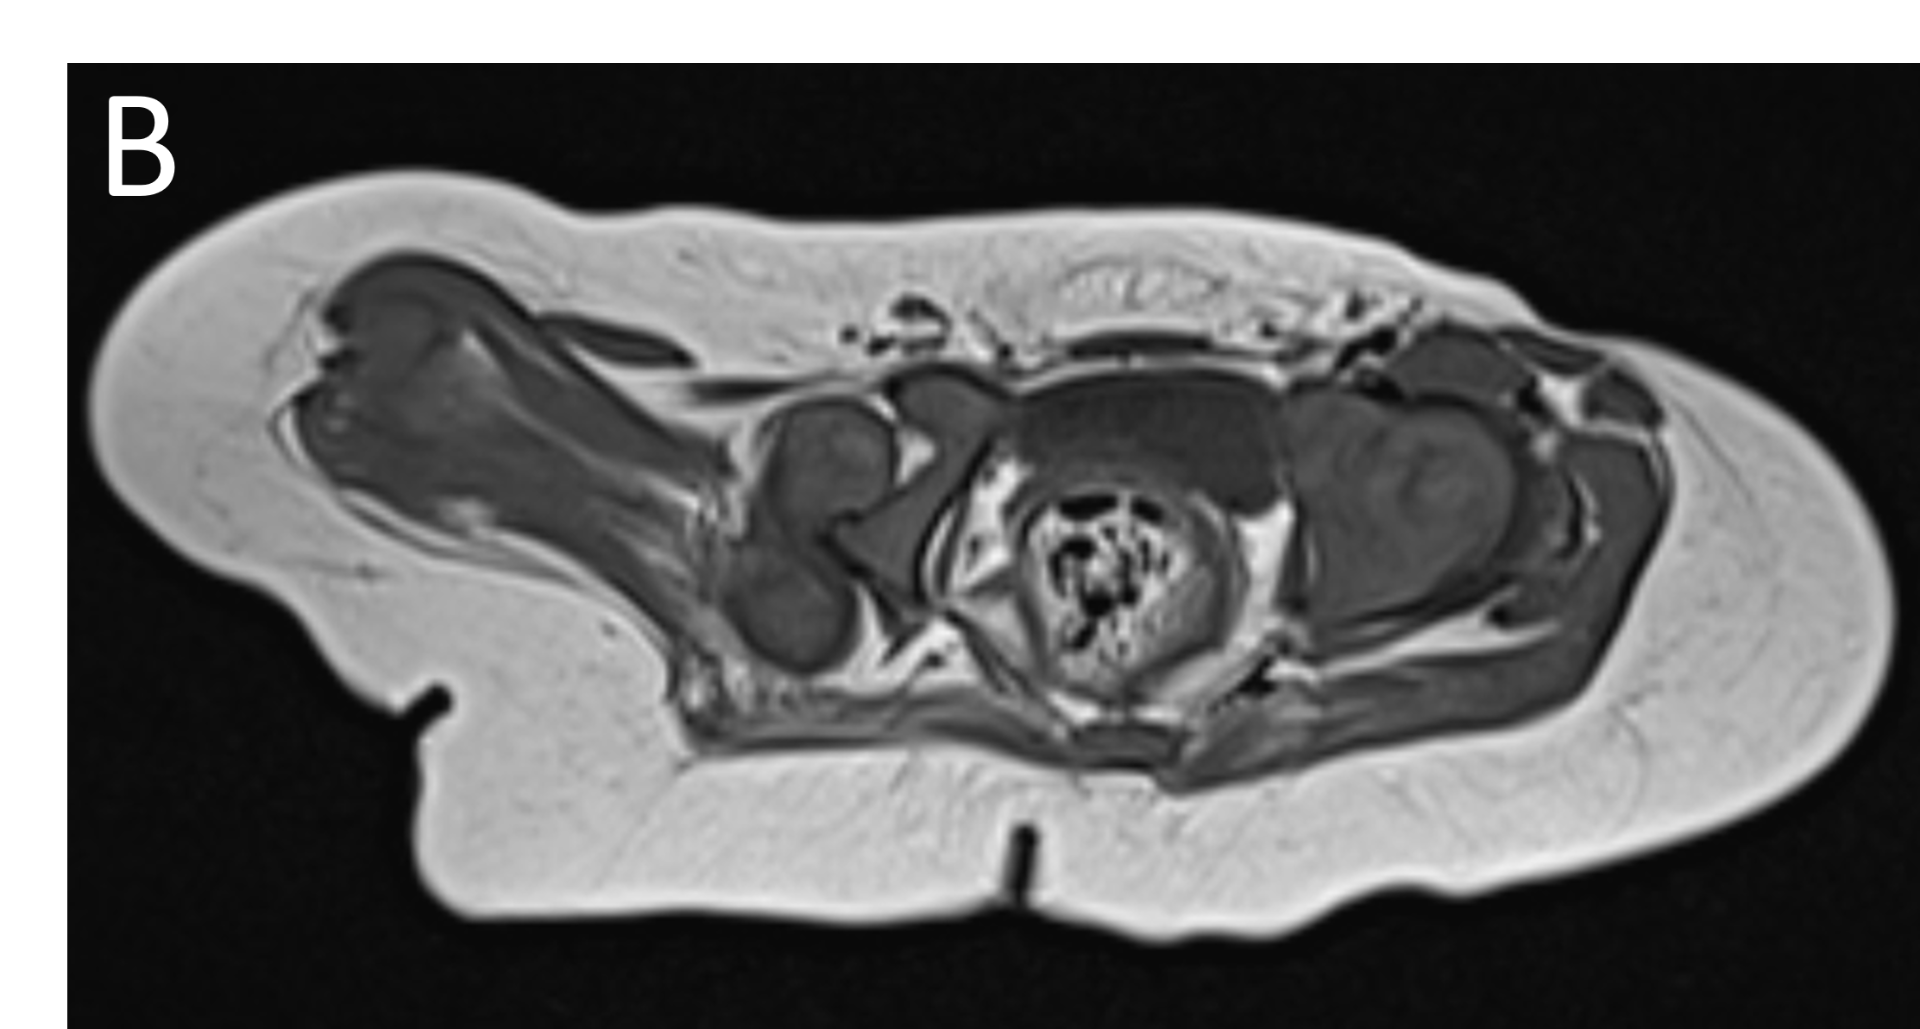

- B.FINDINGS – MR BILATERAL HIPS

- B.LEGENDS – MR BILATERAL HIPS : Generalised atrophy of muscles of thigh and gluteal region on the right compared to the left.